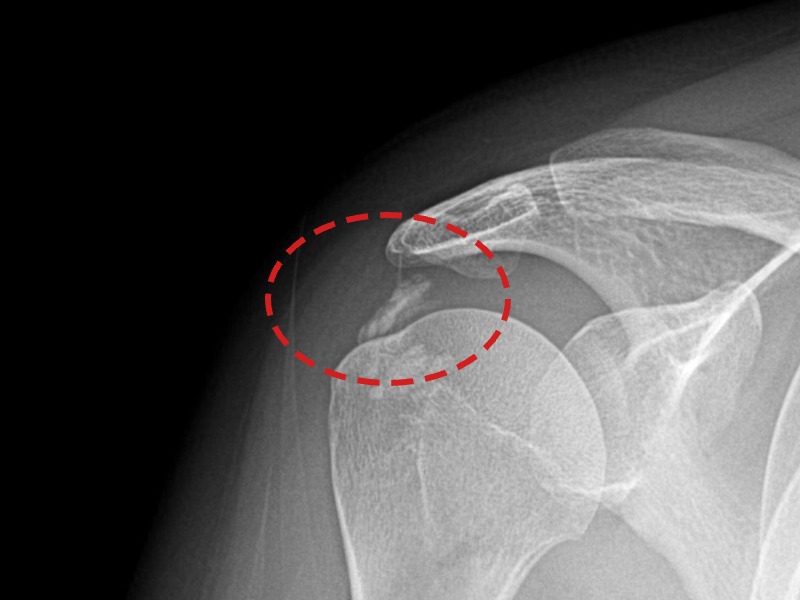

[촬영시기:21.11.04~21.11.09]

[석회분쇄흡입술] 우측 어깨 극심한 야간 통증으로 수면이 불가능해진 50대 여성 환자로, X-ray에서 우측 극상근건 내 석회 침착이 확인되어 석회분쇄흡입술을 시행하였습니다.